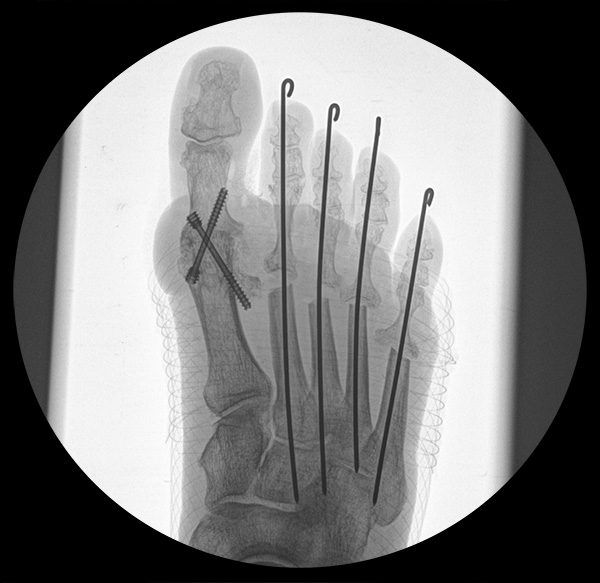

Deutlich bessere Ergebnisse wurden erreicht durch eine Kombination der OP nach Tillmann mit einer Arthrodese des Großzehengrundgelenks oder auch einer Lapidus-Arthrodese 611. Dies wurde bereits 1956 durch Vainio empfohlen, hat sich aber erst in diesem Jahrtausend flächendeckend durchgesetzt 121314.

Zum Lesen der Bildbeschreibung und zur Vollansicht bitte das Bild anklicken.